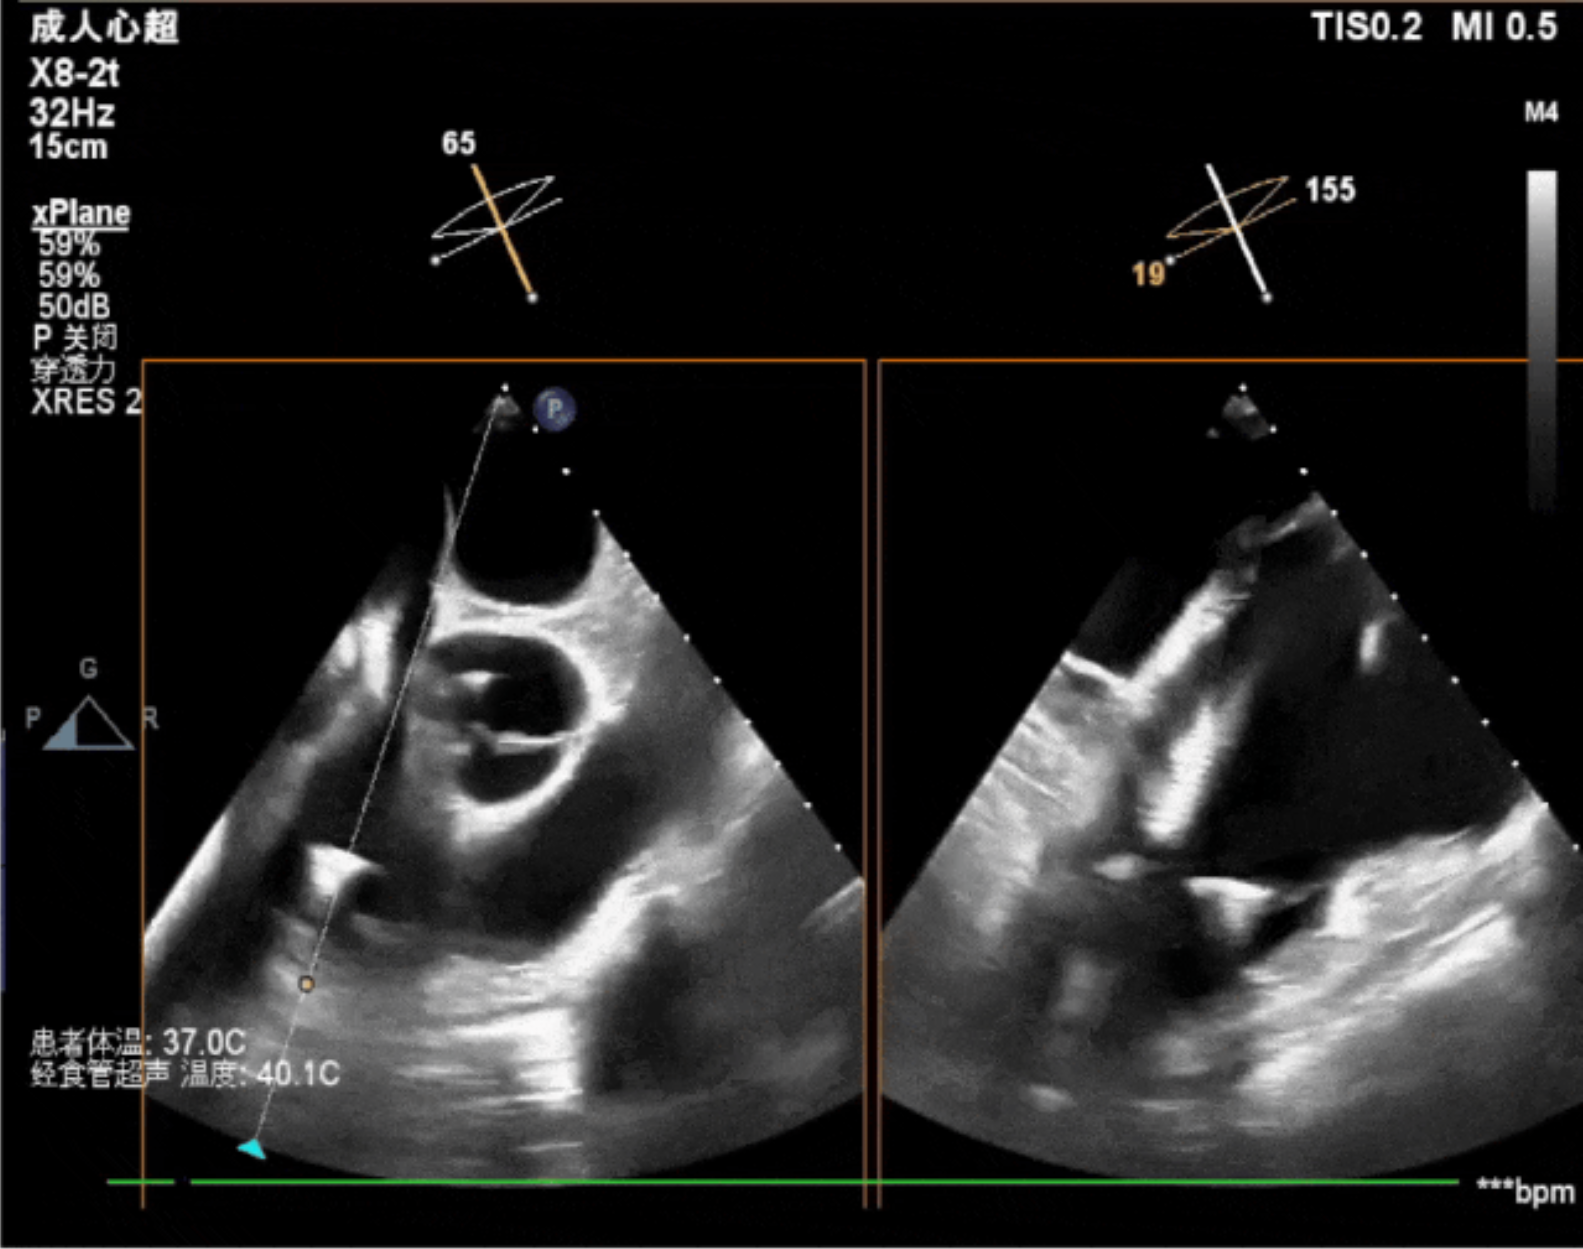

術(shù)中經(jīng)食道超聲輔助下可見LuX-Valve Plus夾持件抓捕瓣葉狀態(tài)良好,夾持件在位,室間隔錨定位置良好,假體瓣膜整體錨定狀態(tài)穩(wěn)固。

術(shù)后即刻經(jīng)食道超聲可見,三尖瓣假體瓣膜位置合適,牛心包瓣葉運動狀態(tài)良好,開閉正常,瓣周及瓣葉對合緣處未見明顯返流,心電圖及心包狀態(tài)較術(shù)前無明顯變化。